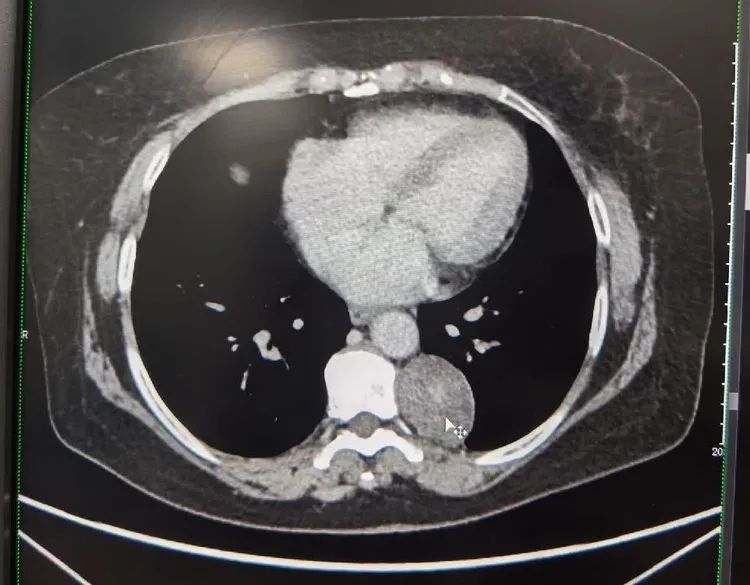

患者胸部增强CT扫描提示:见其左后纵隔旁占位,考虑神经源性肿瘤可能性大。据了解,神经源肿瘤是纵隔内常见的肿瘤之一,占纵隔肿瘤的15%~30%,大部分为良性。目前的病因及发病机制尚不明确,女性患者略多于男性,任何年龄都可以发生,但儿童神经源肿瘤恶性率较高(50%),成人在10%以下。纵隔神经源性肿瘤多发于后纵隔,多数患者无症状。部分患者可有咳嗽、气短、胸痛等症状,治疗以手术为主,放化疗为辅,其预后与肿瘤的良恶性密切相关。

结合各项检查,确诊孙女士系左后纵隔肿瘤。影像见肿块大小约45mm*36mm*48mm,术前无肺功能障碍,集团胸心外科医疗中心高涛涛院长会诊后,决定为其在全麻下行单孔胸腔镜下左侧胸纵隔占位切除术+肋间神经阻滞术。